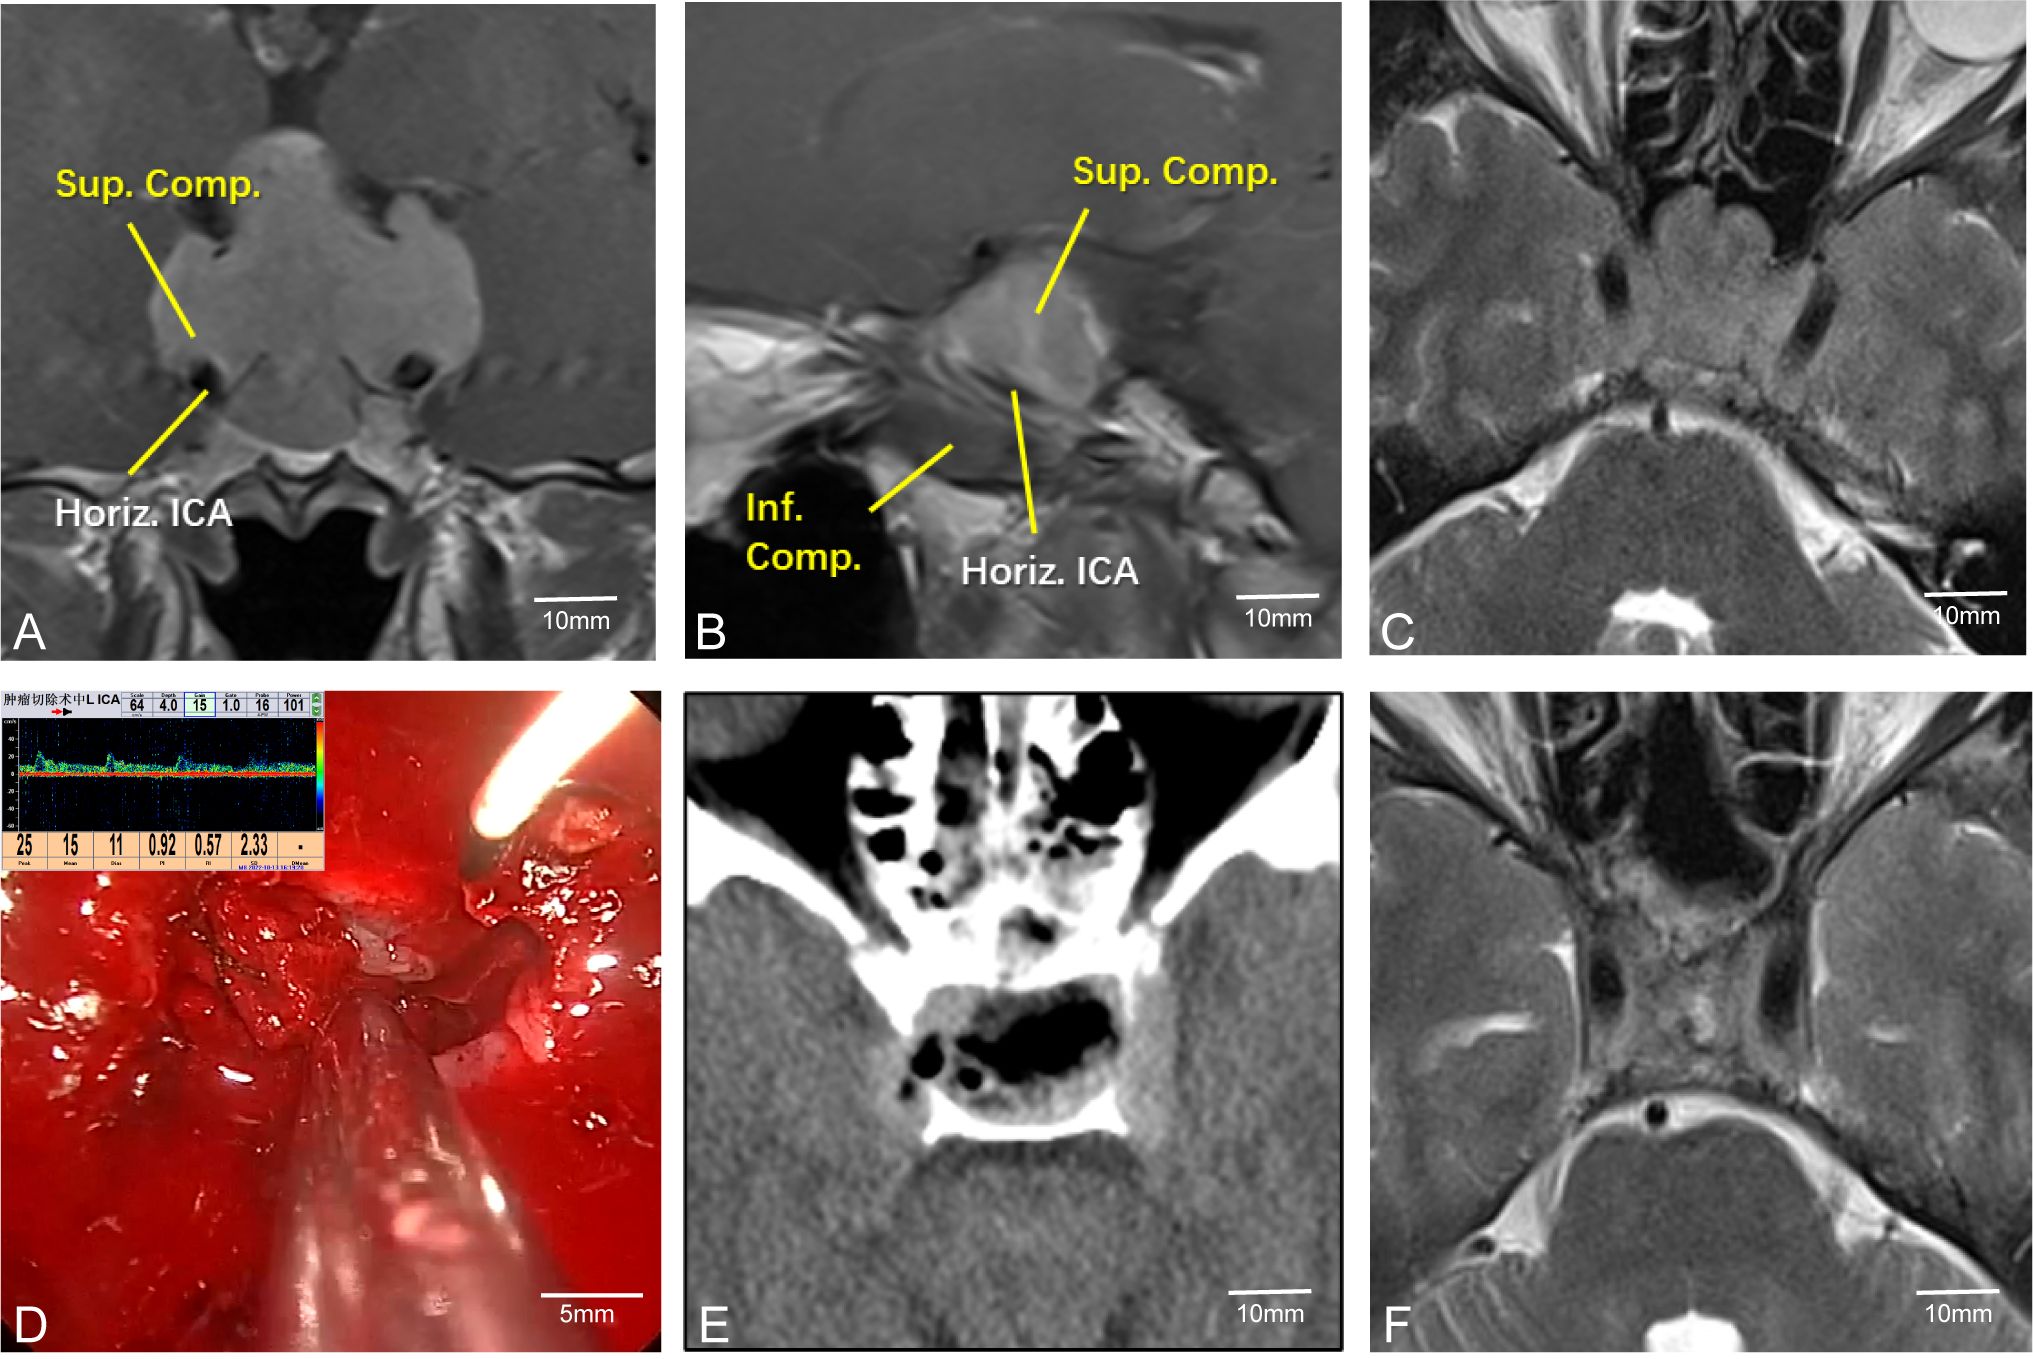

Pituitary tumors with high Knosp grades often increase the difficulty of surgery due to encasement of the C2 or C4 segment of the internal carotid artery (ICA). Intraoperative maneuvers must be extremely careful to avoid damaging the ICA, allowing the removal of tumors hidden in the posterior angle of the ICA and improving surgical outcomes. Therefore, accurately determining the position of the ICA during surgery is crucial. For instance, in Case 24, the left ICA was completely encased by the tumor (Figures 4A–C). During surgery, MVD was used to confirm the position of the ICA (Figure 4D). The tumor was completely resected while preserving the integrity of the blood vessel (Figures 4E, F).

Figure 4. Case 24. Endoscopic resection of complex pituitary adenomas assisted by MVD. (A–C) Preoperative MR Showed that the left ICA was surrounded by the tumor. (D) Intraoperative determination of the position of the left internal carotid artery and the direction of blood flow. (E, F) Postoperative CT and MR demonstrated that the tumor was resected satisfactorily and the blood flow of the internal carotid artery remained unobstructed.